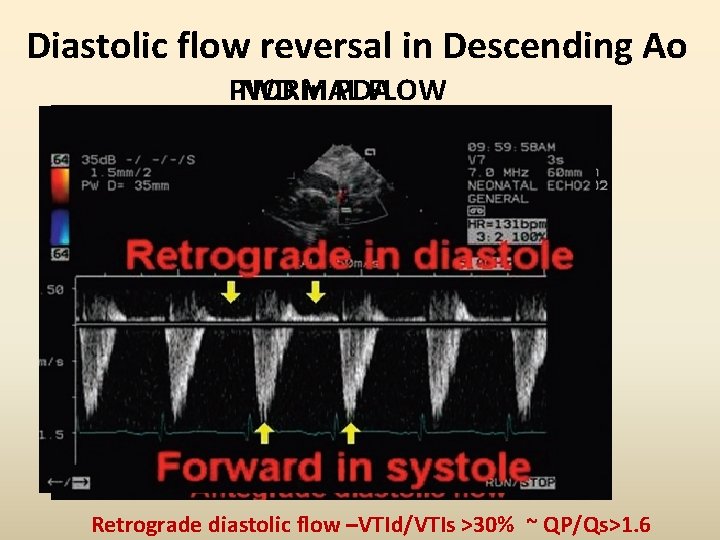

Diastolic flow reversal in Descending Ao PWD NORMAL in PDA FLOW Retrograde diastolic flow –VTId/VTIs >30% ~ QP/Qs>1. 6